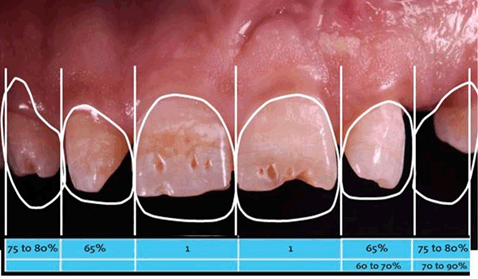

With the assistance of a smile analysis performed using software templates (Figure 4), a partial diagnostic waxing-up of the six maxillary anterior teeth was performed followed by intraoral mock-up for the assessment of the appropriate positioning of the incisal edges.

Figure 4: Digital smile analysis to assess in the diagnostic waxing-up.